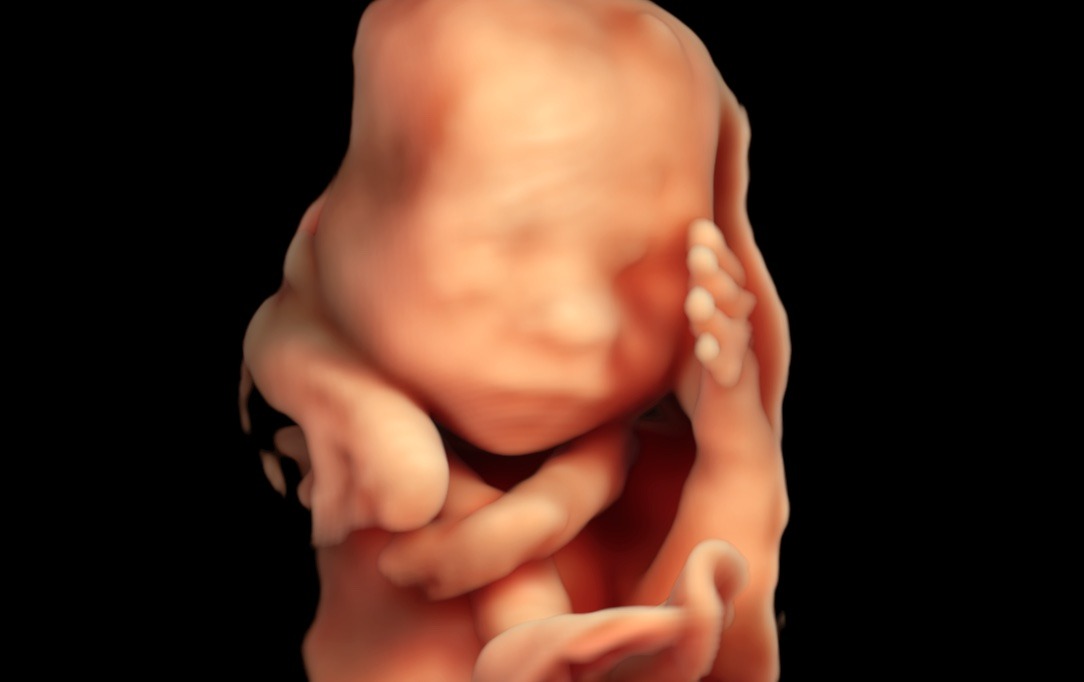

Naše klinika prenatální péče a genetiky nově disponuje nejvýkonnějším ultrazvukovým přístrojem na trhu –Voluson™ Expert 22 od GE Healthcare. Špičkový systém přináší zcela nový standard v oblasti prenatální diagnostiky.

„VolusonTM Expert 22 je přístrojem, který disponuje nejmodernějšími technologiemi pro zobrazování plodu ultrazvukem. Vysoká kvalita obrazu zaručuje mimořádně detailní a přesné zobrazení jednotlivých struktur plodu včetně jeho cévního zásobení. Tyto parametry nejen že zvyšují přesnost naší diagnostiky, ale hlavně posouvají naše možnosti záchytu vrozených vad do časnějších fází těhotenství. Kvalitní 3D/4D technologie zaručuje precizní posouzení prostorových vztahů. Bez její dostupnosti si dnes například nedokážeme představit cílené vyšetření mozku plodu a významně nám dokáže pomoci i v upřesnění celé řady dalších abnormálních nálezů. Takovéto přístrojové vybavení vnímáme jako nepodkročitelnou podmínku pro poskytování prenatální diagnostiky a té nejvyšší možné úrovni, “ prof. MUDr. Ivana Kacerovská Musilová, Ph.D. Odborný garant a gynekolog